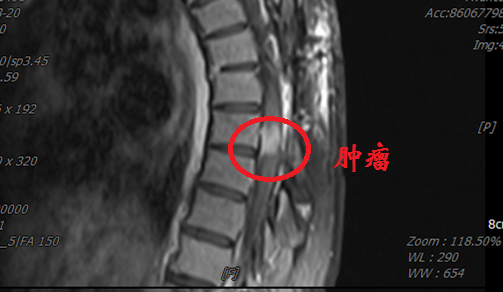

患者李女士(化名)来自西北少数民族地区,罹患胸段椎管内脊膜瘤,此前已在当地医院历经两次手术。近日,患她再次出现行走困难、疼痛难以平卧以及大小便费力,偶有失禁等症。患者首先回到最初就诊的省级医院,胸椎MRI示肿瘤再度复发,鉴于再次手术的难度和风险过高而被建议转院治疗。

几经辗转,患者来到西安交通大学第二附属医院神经外科就诊。郭振宇副主任医师接诊后,详细了解病情,发现“因多次手术,造成肿瘤与神经组织粘连严重,并且椎管腔内外解剖结构不清,再次手术患者瘫痪风险很高,并有可能大小便失禁”。

郭振宇请示上级医师刘重霄教授,并经查体阅片后,刘重霄教授再次给家属讲明了手术意义和风险,家属表示:“我们完全相信你们,医生,我们愿意手术”。随后,在吕健主任主持下,全科进行了深入讨论后,决定为患者进行“第三次手术”。